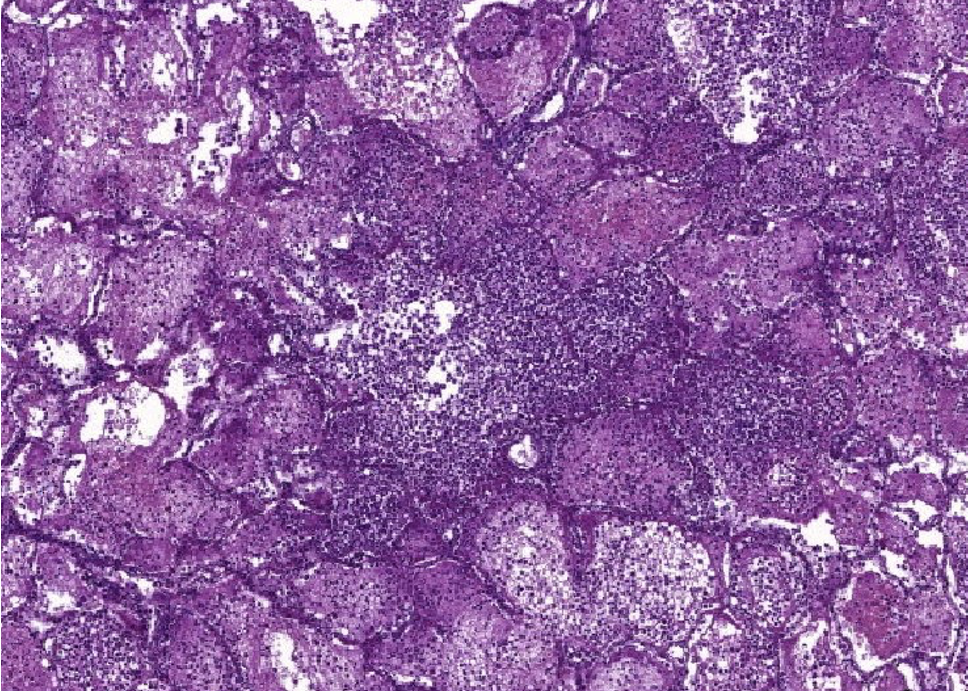

pathologische kenmerken multiple myeloom

mature en abnormale plasmacellen

hypercellulair

anisocytose

nucleoli duidelijk aanwezig

megakaryocyten

voorlopercellen van granulocyten en erythrocyten

vetcellen

osteocytes

multiple myeloom